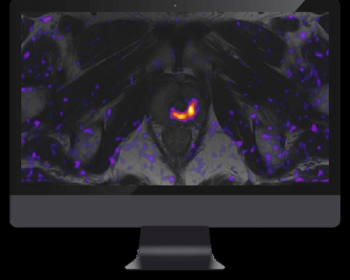

Emphasizing restriction spectrum imaging (RSI), the recently launched prostate MRI software OnQ Prostate may enhance PI-RADS assessments and workflow efficiency.

New prospective research examining the utility of 18F-PSMA-1007 PET/CT revealed comparable sensitivity to mpMRI for detecting clinically significant prostate cancer and a 17 percent higher specificity rate.